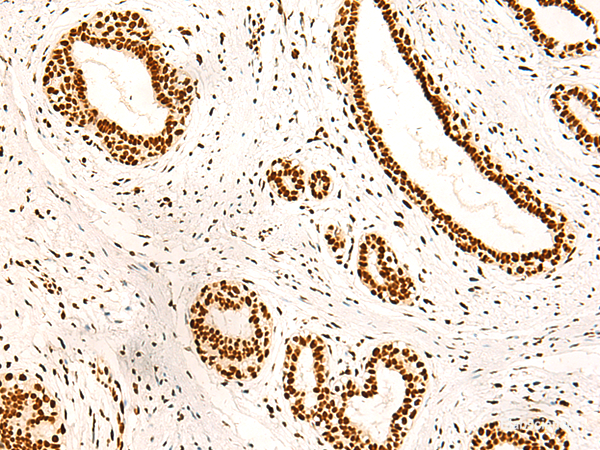

Product information "Anti-ILF3"

| Application: | IHC, ELISA |